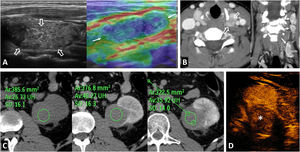

Von Hippel-Lindau syndrome. A 40-year-old male under follow-up for Von Hippel-Lindau syndrome with a genetic diagnosis and a previous left nephrectomy. In the follow-up with ultrasound and colour Doppler (A), a solid nodular lesion measuring 41 mm (arrows) is detected, confirmed by CT in the nephrographic phase (B and C) and susceptible to selective resection. Renal cysts are also visible (*).

Birt-Hogg-Dubé syndrome. A 68-year-old male. Incidental finding in an ultrasound examination. (A) Ultrasound centred on a lesion. In B-mode (arrow) it is discreetly hypoechogenic, with contrast enhancement (red ROI), purely intravascular, almost as intense as that of the renal parenchyma (yellow ROI), both in the static image and in the time-intensity curve (not shown). Core needle biopsy was performed on this lesion and on another lesion (not shown), with histological diagnoses of a chromophobe cell renal carcinoma and an oncocytic lesion. (B) CT Multiple focal bilateral renal lesions of various sizes and well demarcated (at least six were identified) with moderate enhancement, somewhat weaker than that of the renal parenchyma and more intense in the corticomedullary phase (arrows). One had some small focal calcification (not shown). Thin-walled cysts are also visible at the lung bases (arrowheads). (C) MRI centred on the larger lesion (arrows). It shows signal intensity in T1 (similar for in-phase and opposed-phase sequences) and T2, as well as moderate water diffusion restriction, with an average ADC value of 0.91 × 10−3 mm2/s and clearly less intense enhancement than that of the renal parenchyma in the time-intensity curve (ROI and red and yellow curves, respectively). The genetic study confirmed a germline mutation of the FLCN gene in heterozygosis.

Renal metastasesThe kidney is the eighth most common organ in which metastases occur, with the lung being the most common primary organ. This is seen on imaging in 0.9% of cases (7–20% in autopsies), slightly above the frequency of incidental RCC (0.6%), usually in the context of advanced oncological disease. Although dependent on the primary tumour, growth is generally faster, behaviour tends to be more infiltrative and endophytic, and enhancement is poorer and later than for RCCs42 (Fig. 12).

Renal metastases and mimics. (A) Renal metastases of squamous-cell carcinoma of the lung (arrow), exhibiting multiple renal masses with poor enhancement and infiltrative behaviour (*). (B) Renal metastases of adenocarcinoma of the gallbladder with extensive infiltration of the adjacent liver parenchyma (arrows) and extensive peritoneal carcinomatosis, also within an inguinal hernia (hollow arrows). The renal lesions (*) behave similarly to the primary neoplasm, with moderately intense and heterogeneous enhancement, and abundant tumour necrosis. In this case, the lesions have a more expansive behaviour. (C) Clear cell renal cell carcinoma mimicking breast carcinoma metastasis in a 64-year-old woman undergoing oncological follow-up due to her medical history. Exophytic, expansive renal cortical lesion with enhancement almost as intense as that of the parenchyma (arrows). A retrospective review of previous studies showed that it was present in a study performed two years earlier (dashed arrow), with slower growth than expected for metastasis. The diagnosis was confirmed following percutaneous biopsy and tumour removal. (D) Contralateral renal metastases of clear cell carcinoma (ccRCC) or Von Hippel-Lindau? An 82-year-old female underwent a right nephrectomy for ccRCC. CT images show numerous markedly enhancing contralateral renal nodules with cystic appearance and thick walls, which is the usual appearance of lesions in Von Hippel-Lindau syndrome. However, hypervascular metastases coexisted in both the left adrenal region (arrowhead) and lung (not shown). The patient died without a confirmatory genetic diagnosis.

Lymphomas, usually of the B-cell non-Hodgkin variety, have renal involvement that has been radiologically confirmed in 1–8% of cases (30–60% in autopsies). They are usually bilateral and involve lymph node and/or other organ disease. In the literature, diffuse infiltration is the most common histological pattern, and imaging reports most frequently describe multifocal lesions.43 In our experience, perirenal infiltration is the most common pattern, often extending into the renal sinus. The lesions are infiltrative, homogeneous and hypoenhancing with marked diffusion restriction (Fig. 13). Similar findings are seen in certain types of leukaemia.

Renal lymphoma. (A) Diffuse infiltration of both kidneys (arrows), in addition to infiltration also demonstrated by a lymphoma of the prostate (+), with the stem of a bladder catheter in its urethral section, and a lymphoma of the gastric wall (*). (B) Multiple and bilateral nodules with discrete enhancement (*). (C) Perirenal solid masses (*) with discrete enhancement, which infiltrate the superficial renal parenchyma (arrows) and penetrate the renal sinus (+), causing discrete hydronephrosis (arrowheads), albeit sparing the vessels (not shown). (D) Peripelvic and renal sinus infiltration (*), in this case accompanied by abundant retroperitoneal and mesenteric lymphadenopathies (+). (E) Infiltration of the renal sinus, with significant water diffusion restriction, high signal in the diffusion sequence with B = 800 s/m2 and low signal in the apparent diffusion coefficient (ADC) map (arrows).